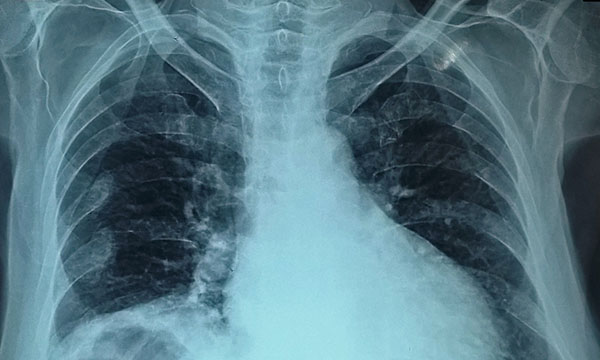

Chilaiditi sign and syndrome are uncommon conditions and often misdiagnosed. They are clinically significant, however, because they can result in a range of complications, including bowel volvulus, perforation and obstruction. When patients are symptomatic, treatment is usually conservative and surgery is rarely indicated unless there is a suspicion of ischaemia, or if conservative management does not resolve other signs and symptoms. This article describes Chilaiditi sign and syndrome, and presents four case studies to illustrate the relevant signs and symptoms.

Image